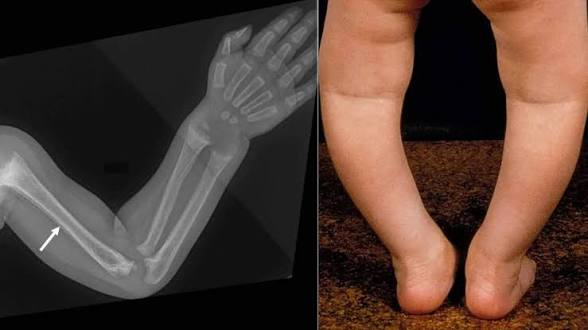

اليكم .. سبب لين العظام عند الأطفال وعلاجه

✍/ أسماء أحمد محمد نقدم لكم في هذا المقال معلومات عن لين العظام عند الأطفال فهو مرض من الأمراض التي تسبب شكل من أشكال الإعاقة. ويتسم مرض لين العظام بأن العظام تظهر مقوسة أو غير مستقيمة وفي حالة عدم تمكن الأم من ملاحظة إصابة الطفل بلين العظام حتي تتمكن من علاجه في الصغر فانه قد يلازم […]